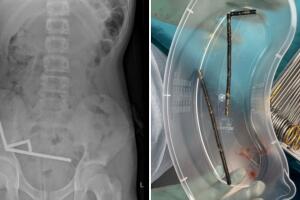

- article1 Min ReadOctober 24, 2025 03:00 PMLos médicos informaron que la presión de los imanes había causado necrosis en cuatro zonas del intestino delgado, por lo que los cirujanos realizaron una operación para retirar el tejido muerto y extraer los imanes.